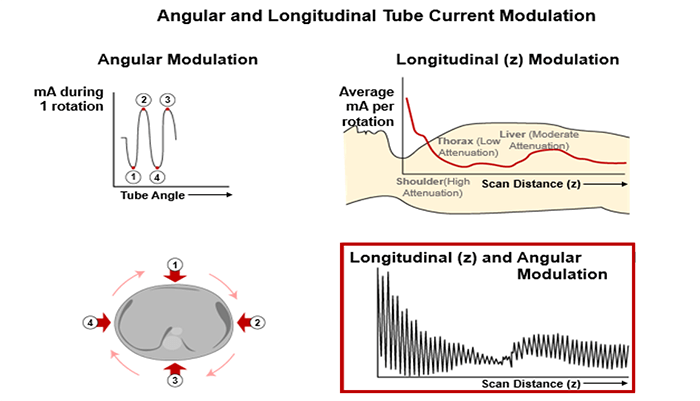

mA Modulation

Automatic correction adjusts dose as a function of patient size and the anterior-posterior and lateral directions. The lateral projection generally encounters more tissue thickness than a PA view. This is known as mA modulation and the mA is increased and decreased as the patient is scanned. Most systems use an average mA to calculate the CTDIvol.

This is an automatic dose-response based on patient anatomy (scout view). Since the human body is not cylindrical, its contours and tissue densities must be taken into account.

Automatic correction adjusts dose as a function of patient size and the anterior-posterior and lateral directions.